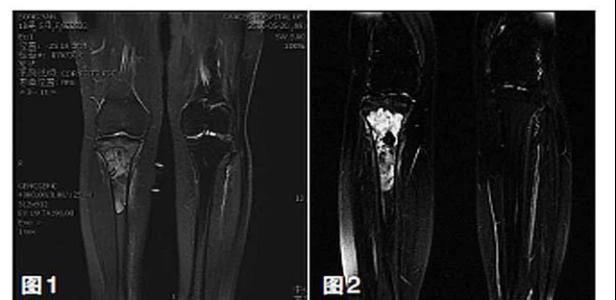

骨肉瘤是最常見的骨原發性惡性骨腫瘤,好發于兒童和青少年,四肢為其主要發病部位。目前,保肢治療被認為是肢體骨肉瘤的標準治療方法以及有效的基礎治療手段。我國幅員遼闊,但醫療技術發展不平衡,需要理論涵蓋充分、技術指導性強且適用于骨肉瘤治療領域的保肢治療指南。因此,“四肢骨肉瘤保肢治療指南”從保肢治療定義、手術方法、療效評估、術后處理與并發癥防治、康復指導與隨訪建議等方面系統介紹四肢骨肉瘤保肢治療方法,為規范和推進保肢手術技術發展、提高保肢治療成功率保駕護航。

保肢治療指經典型骨肉瘤在多學科團隊醫生共同努力下完成的新輔助化療、保肢手術和輔助化療等一系列治療總稱,其目的是在提高患者生存率的前提下,減少局部復發、盡量保留良好的肢體功能。肢體經典型骨肉瘤保肢治療方法如下圖所示:

新輔助化療的目的是盡早殺滅遠處微小轉移灶,縮小腫瘤及周圍炎性水腫反應區,以利于后續的保肢手術;觀察腫瘤對化療的敏感性,為進一步指定個體化的術后化療方案奠定基礎。骨肉瘤新輔助化療下的保肢治療如下圖所示: